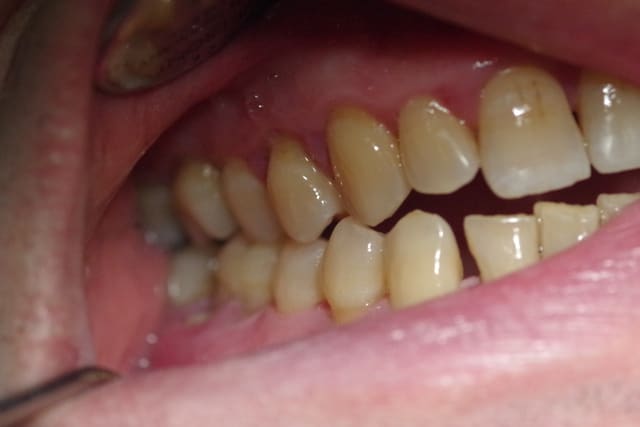

Le patient de 65 ans n'a plus d'occlusion sur le secteur ant et sur le secteur postérieur gauche.

L'occlusion ne se fait que sur les 5, 6 et 7 côté droit.

De ce fait la surcharge occlusale sur la 46 a entraîné une lyse osseuse importante qui contre indique la conservation de cette dent.

J'ai d'abord pensé adresser le patient pour une rééducation linguale ( kiné ou orthophoniste) car le patient a une langue très puissante qui a entraîné l'inocclusion totale des secteurs antérieurs et latéraux ( côté gauche).

PS2 Les dents, sur les secteurs postérieurs, se sont considérablement écartées sans doute due à la pulsion linguale.